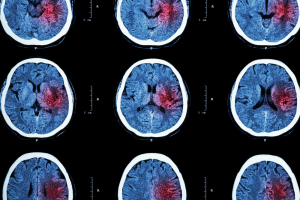

Cosa succede al movimento dopo un ictus

Un ictus interrompe il normale funzionamento di alcune aree del cervello, alterando il modo in cui il movimento viene controllato.

Il risultato può essere debolezza, rigidità, perdita di coordinazione o difficoltà nel compiere anche gesti semplici.

Non si tratta solo di “forza” che manca, ma di un problema più profondo:

👉 il sistema nervoso fatica a organizzare correttamente il movimento.